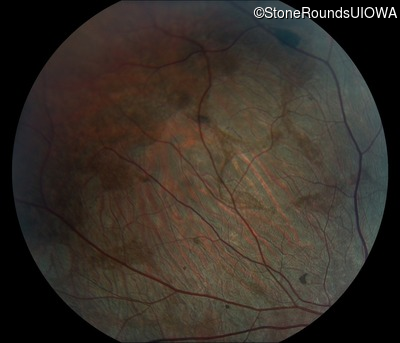

Visit at age: 15 years

Fundus Photography - Right - 20/20 -1 sc

Fundus Montage - Right - 20/20 -1 sc